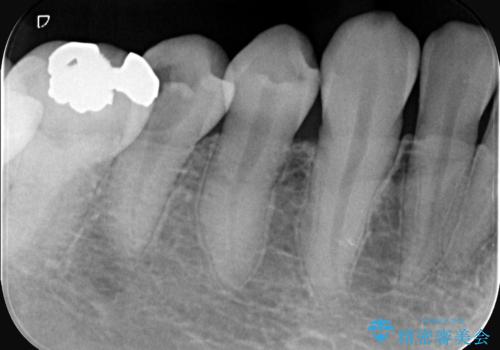

- 虫歯が大きく歯が欠けている状態でした。 そこに食べ物も詰まっている状態でした。

虫歯を除去後、精密根管治療を行い、オールセラミッククラウンで治療を行いました。

虫歯が大きく神経まで到達していました。将来根尖性歯周炎にならないよう徹底的に神経をとり洗浄したうえで被せ物をしています。